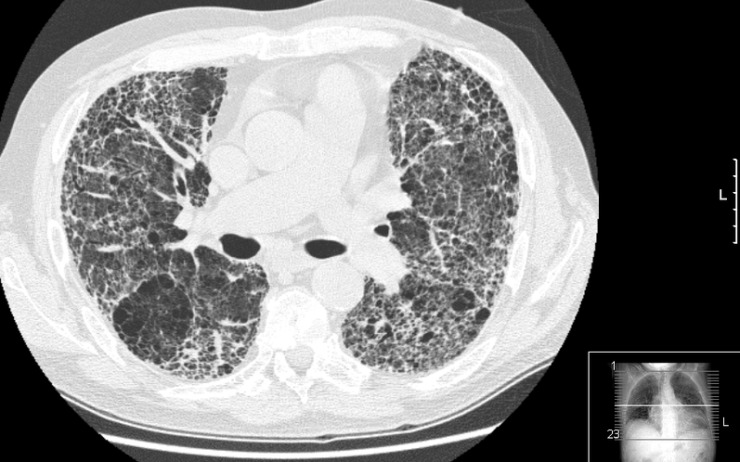

Důvodem, proč plicní lékaři zorganizovali dny otevřených ambulancí, je snaha odhalit zavčas zákeřnou nemoc, která ročně v České republice zabije desítky pacientů. Poškozuje plicní sklípky, jizví je – bere plochu k dýchání, plíce tuhnou a člověk se nemůže nadechnout. Postup nemoci brzdí léčba, která je v tuzemsku pouhých 5 let. Pacienti se k ní však často nedostanou, protože se nemoc odhalí pozdě.

Projevy IPF lékaři často zaměňují za chronickou obstrukční plicní nemoc, zápal plic či srdeční selhání. Bez správné léčby přitom IPF obvykle zabíjí do 3 let. S léčbou ale může pacient vzdorovat roky a zvyšuje se jeho šance, že se dočká transplantace plic.

Nemoc se ohlašuje zprvu nenápadně, člověk se začne zadýchávat do schodů, později i při chůzi či hovoru, v pokročilém stádiu má pocit nedostatku vzduchu při běžných denních činnostech a v závěru věnuje veškerou energii tomu, aby se nadechl. „Rychlost a včasnost diagnózy je pro další průběh nemoci naprosto klíčová. V časných a málo pokročilých fázích nemoci totiž dovedeme plicní fibrózu a úbytek plicních funkcí zpomalit podáním účinných léků. Proto by ambulantní lékaři měli při prvním podezření okamžitě pacienta odeslat do některého ze 17 Center pro diagnostiku a léčbu intersticiálních plicních procesů, kam nyní doputuje pouhá čtvrtina z odhadovaných 2 000 pacientů s IPF," doplňuje prof. MUDr. Martina Vašáková, PhD, přednostka Pneumologické kliniky 1. lékařské fakulty UK a Thomayerovy nemocnice v Praze a předsedkyně Sekce pro intersticiální plicní procesy (SIPP) České pneumologické a ftizeologické společnosti.